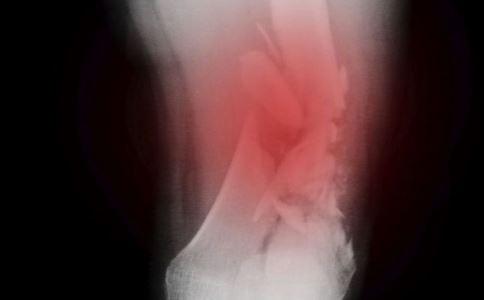

②X线片上显现椎体后缘骨质增生

③X线片显现节段性不稳定或枢椎关节骨质增生

②X线片上颈椎显现曲度改动或椎间关节不稳等体现